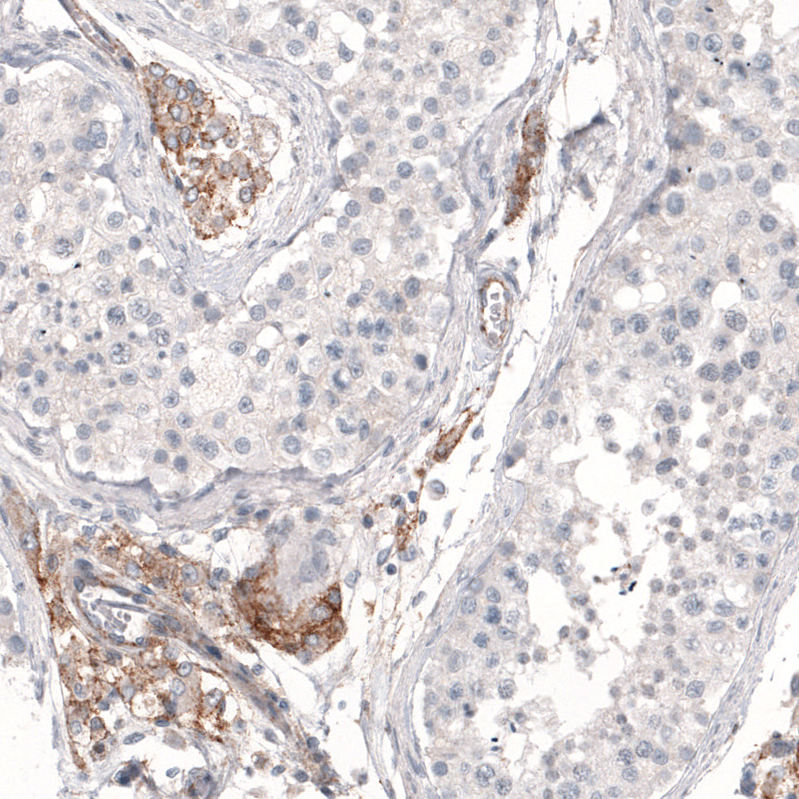

Immunohistochemistry analysis in human kidney and skeletal muscle tissues using AMAb91233 antibody. Corresponding THSD7A RNA-seq data are presented for the same tissues.